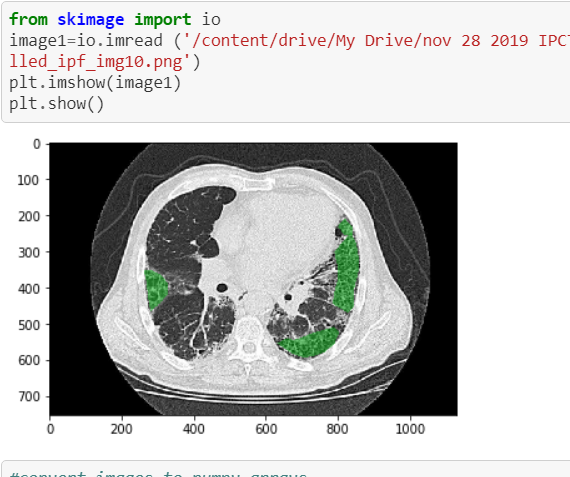

We used ResNet-50 convulational neural network (CNN) in this experiment for deep learning for image recognition and classification. The model layers are as shown below. We used optimizer= ‘Adam’.